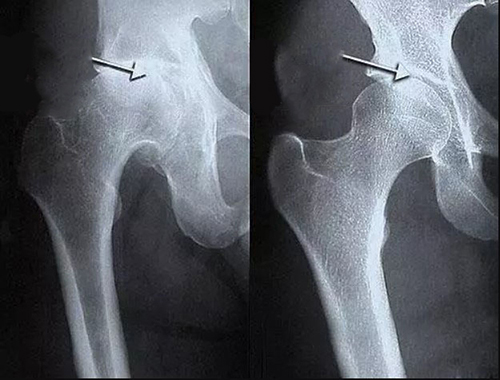

สาเหตุหลักของโรคข้อ คือการตกตะกอนของผลึกเกลือในข้อ เนื่องจากระบบไหลเวียนโลหิตและของเหลวไขข้อ (synovial fluid) เสื่อมลง:

- กรดยูริก (Urate crystals) ทำให้เกิดโรคเกาต์

- แคลเซียมเกาะกระดูก (Osteophytes) คือตัวการของโรคข้อและกระดูกกว่า 97% เช่น โรคข้ออักเสบ โรคข้อเสื่อม โรคกระดูกอ่อน โรคกระดูกพรุน โรคไขข้ออักเสบ โรคถุงน้ำในข้ออักเสบ และแม้แต่ซีสต์ของปมประสาท

เมื่อเกลือเหล่านี้เกาะอยู่บนพื้นผิวของข้อต่อ คราบเกลือเหล่านี้เหมือนกระดาษทรายที่ทำลายเนื้อเยื่อรอบโดยรอบ กระดูก และกระดูกอ่อน เมื่อผลึกโตขึ้น เกลือจะเริ่มทำลายเนื้อเยื่อของกล้ามเนื้อ เอ็น หลอดเลือด และเส้นเลือดฝอย ทำให้เกิดการอักเสบ ติดเชื้อ บวม ก่อให้เกิดการอักเสบและปวดอย่างรุนแรง

ในกรณีรุนแรง การสะสมเกลือจำนวนมากอาจทำให้กระดูกหักได้ง่ายเมื่อมีการเคลื่อนไหวอย่างกะทันหัน ส่งผลให้พิการและข้อต่อไม่สามารถเคลื่อนไหวได้